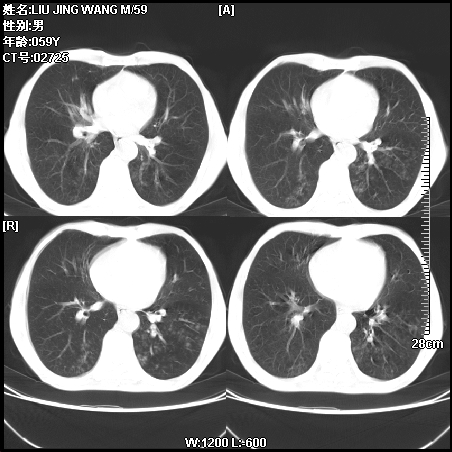

肿瘤科住院病人,都有食管癌史,都有放化疗治疗,两下肺病变是转移灶?还是其他原因造成?请老师指点

病例一 现呼吸困难,经抢救多次,咳嗽咳痰,发现食管癌2个多月